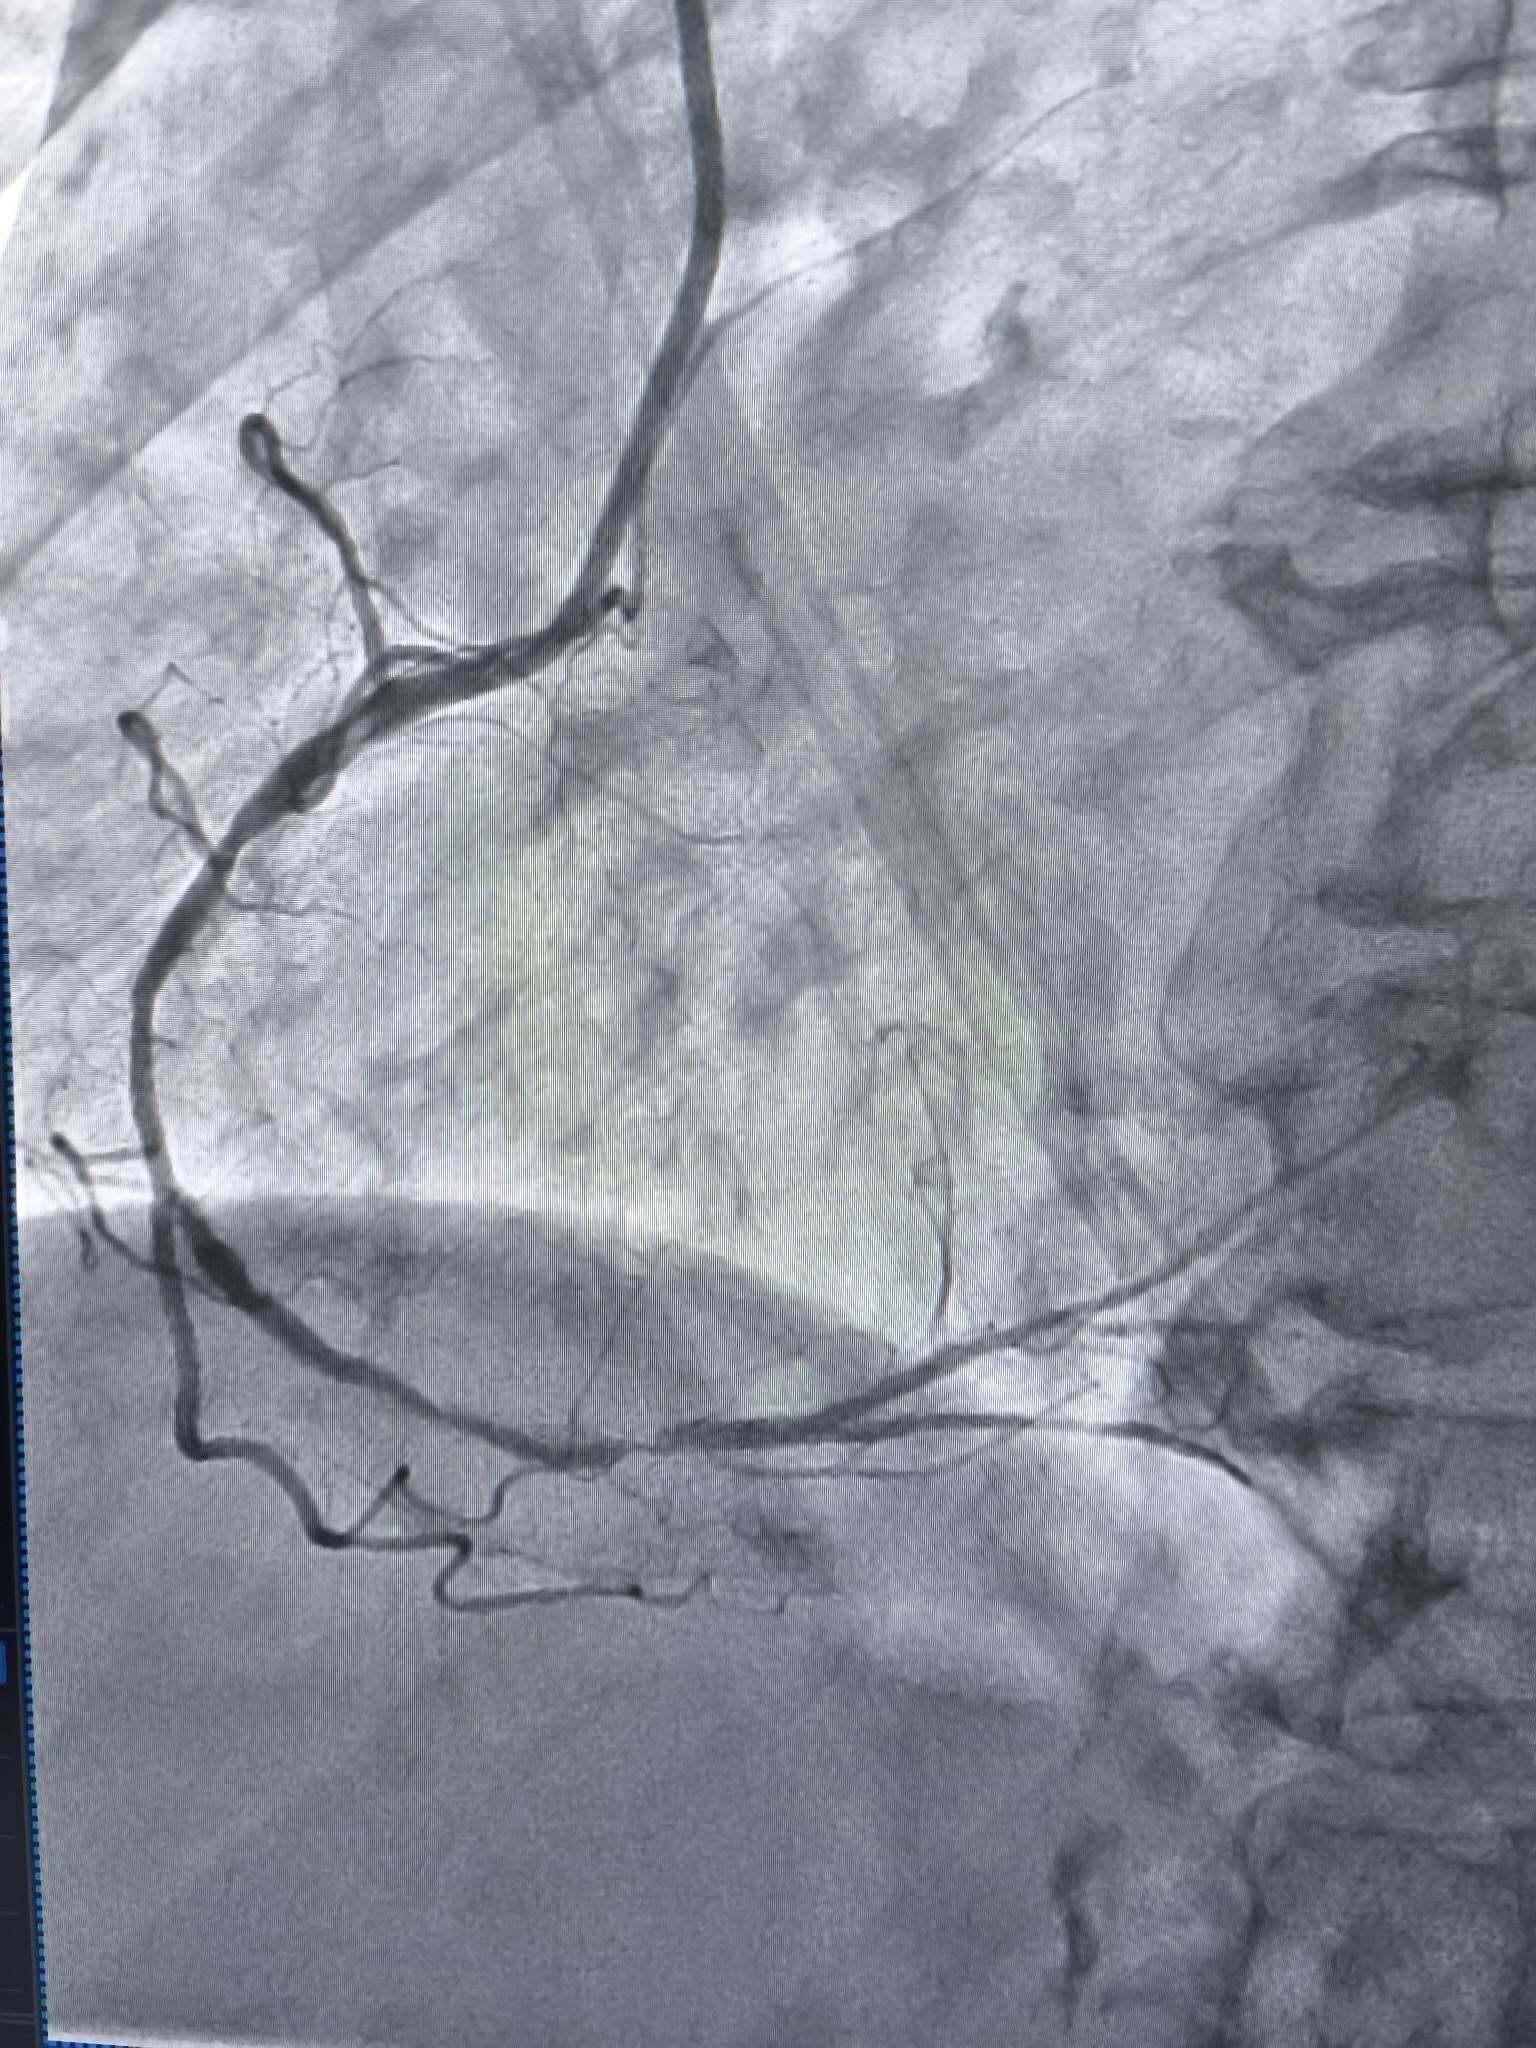

У таких ситуаціях на допомогу приходить ротаблятор – спеціальний пристрій із буром, покритим діамантовим напиленням. Він дозволяє «модифікувати» кальциновану атеросклеротичну бляшку, фактично шліфуючи її та відновлюючи можливість для подальшого стентування судини. Саме таким методом лікарям вдалося ліквідувати перешкоду в артерії та успішно імплантувати стенти.

Це втручання стало важливим кроком для нашої лікарні та всієї області. Ротаційна атеректомія застосовується у найскладніших випадках кальцинованих уражень коронарних артерій, коли стандартна ангіопластика неефективна. Виконання такої процедури означає, що пацієнти Тернопільщини можуть отримати сучасну високоспеціалізовану допомогу без необхідності їхати в інші регіони, – наголосив Богдан Маслій.

Фото Тернопільської обласної клінічної лікарні